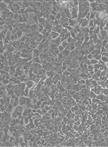

Patient-derived organoids (PDOs) are 3D structures that precisely replicate the microenvironment and cellular composition of endometrial tissue, providing a clinically relevant model for studying specific histologic and molecular subtypes of EC [7–11]. This is particularly valuable for the rarer and more aggressive EC subtypes that disproportionately affect minority populations, especially African American women [2,12–14]. Additionally, the establishment of PDOs addresses the limitation of tissue samples by providing a sustainable cellular resource for ongoing research [15]. PDOs have been shown to maintain their phenotype and genotype through multiple passages, making them reliable models that preserve biological integrity over extended periods in culture [16,17]. However, there remains a need to enhance organoid culture techniques, as organoid cultures may exhibit heterogeneity and variable complexity in cellular composition, as well as poorly controlled morphogenesis during the self-assembly process [18].

Here, we present an optimized method for establishing, expanding, and banking endometrial organoids derived from patient tissue samples of normal endometrium and endometrial cancers.